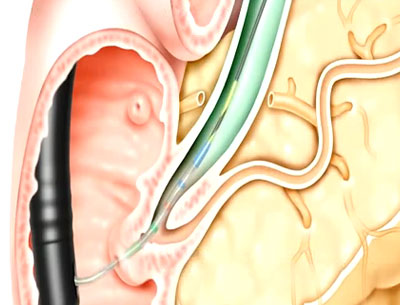

Animación de RX Biliary System™

Esta animación sobre el procedimiento ofrece una descripción general sobre cómo usar el sistema de guía corta biliar RX.